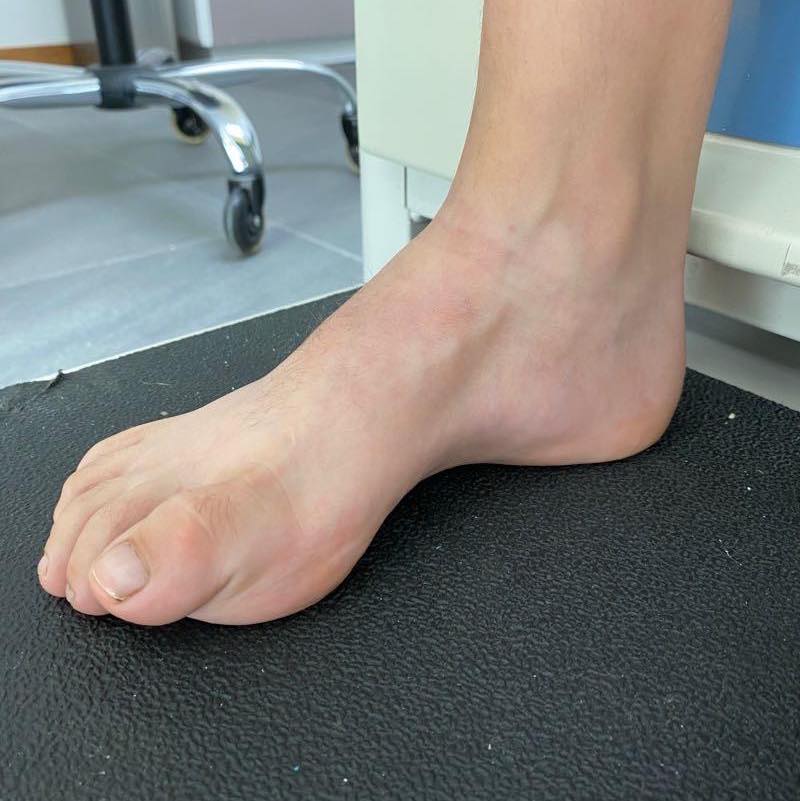

Pie plano infantil

El tratamiento debe ser enfocado solo a aquellos pies que sean dolorosos y que presenten una deformidad importante que impida el uso de calzado habitual. El mejor tratamiento es la rehabilitación y para aquellos que sean rígidos será necesario estudiarlos para descartar la coalición tarsal o alguna otra enfermedad.

Consulta y desarrolo de nuestros pacientes despues de ser intervenidos, lo que muestra la evolucion y avances desde la primera vez que nos visitaron